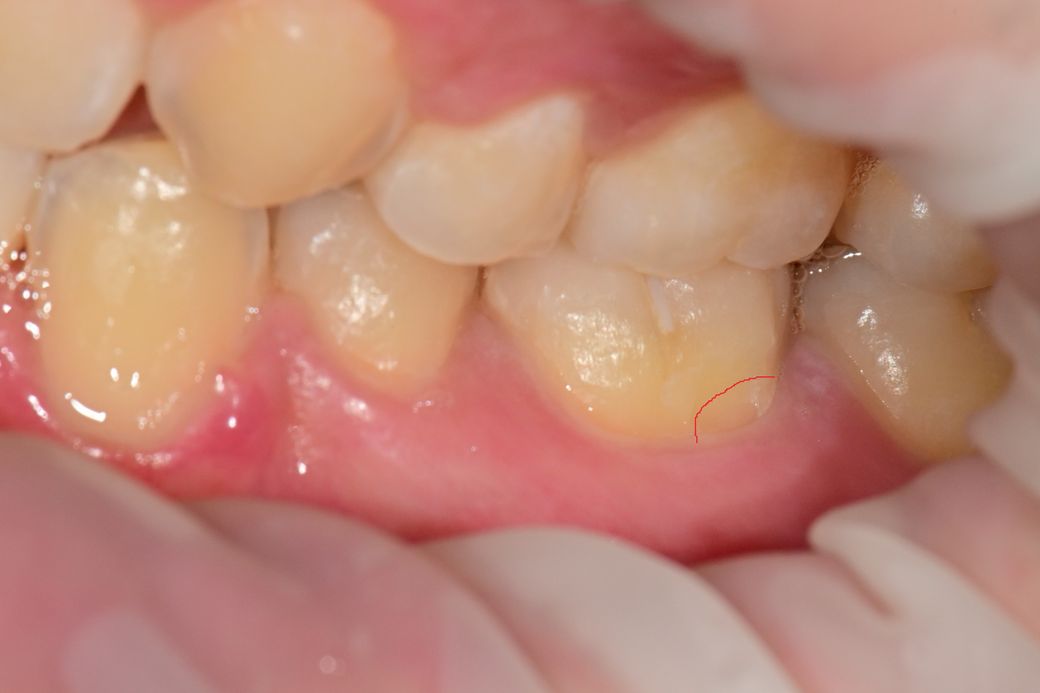

치경부마모증때문에 이가 시려서 (왼쪽 하악 끝에서 2번째 어금니) 치과 방문하니 법랑질이 떨어져나갔다고 합니다

사진처럼 크게 진행되진 않았는데 치과에서 gi는 불가능하고 레진이나 본드필만 된다고 합니다

빨간색으로 표시한부분입니다

• 1번 째 사진

해당 부위는 GI로 메꾸기에는 너무 작은 범위로 보입니다. 쥐어의 경우에는 어느정도 표면적이 나오거나 부피가 있어야 강도가 유지되기 때문에 사진과 같은 얇은 부위를 수복하는데 적합하지 않을 것으로 생각됩니다.

치경부 마모증이 미세하다고 gi가 안되는 것은 아니지만 쉽게 떨어질 가능성이 높습니다.

깨져나간부위가 너무 작아서 레진이나 gi 재료 상관없이 잘 떨어질 것 같습니다. 한다면 레진으로 좀 더 정교하게 하여 조금이라도 유지력을 높이는 것이 좋을 것 같습니다만 또 반대로 생각하면 금방 떨어질 수 있기에 보험되는 재료인 gi로 하자고 하는 치과도 있을 것입니다. gi를 강력히 원한다면 타 치과 알아보시기 바랍니다.